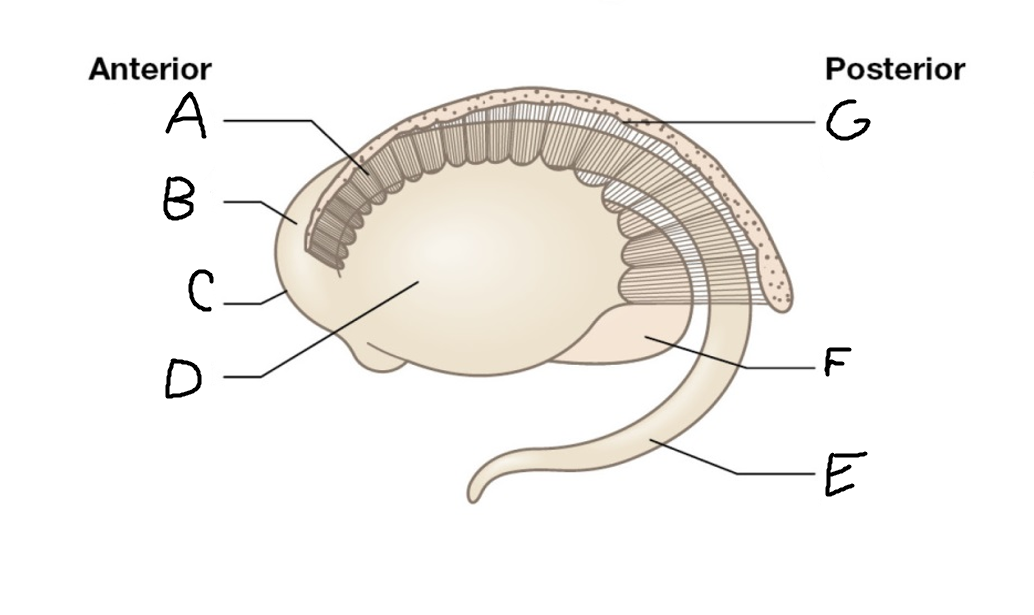

A

caudate nucleus head

C

caudate tail

D

globus pallidus (internal segment)

E

globus pallidus (external segment)

F

putamen